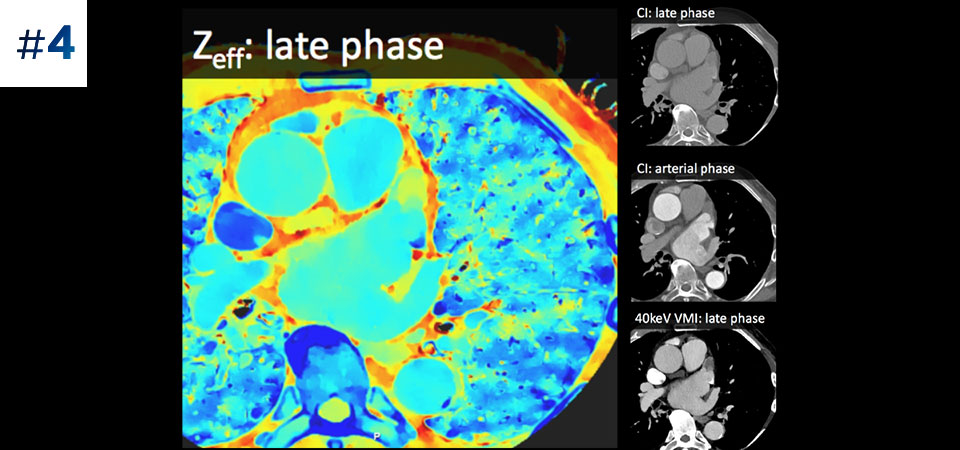

With detector-based spectral, you acquire multiple layers of data—conventional and spectral—within a single exposure and without special scan modes for improved tissue characterization and visualization.

Reduced follow-up exams Improved tissue characterization and visualization may reduce the need for follow-up scanning for sub-optimal exams and incidental findings.

Can you solve the mystery diagnosis using spectral?

Go beyond conventional CT. See how layers of spectral-detector results can enhance your diagnostic confidence.